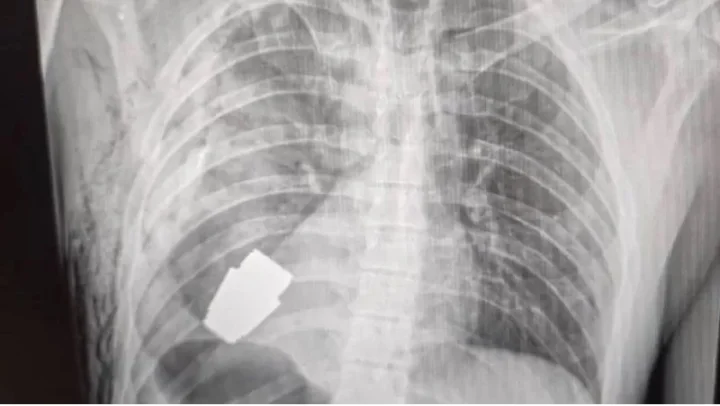

सैनिकाच्या छातीतून काढला न फुटलेला ग्रेनेड

युक्रेनमधील एका सैनिकाच्या छातीमधून न फुटलेलं ग्रेनेड काढण्यात आलं आहे.

युक्रेनच्या सैनिकी वैद्यकसेवेने फेसबूकवर त्याचा एक्सरे फोटो प्रसिद्ध केला आहे. या सैनिकाच्या हृदयाच्या अगदी जवळ हे ग्रेनेड असल्याचं दिसतं.

हे ग्रेनेड त्या सैनिकाच्या छातीत कसं गेलं हे अद्याप समजलेलं नाही. पण ते VOG ग्रेनेड असल्याचं समजतंय. ते 4 सेंमी. आकाराचे असून त्याचा 400 मीटर अंतरापर्यंत मारा करता येतो.

ही शस्त्रक्रिया मेजर जनरल आंद्री वर्बा यांनी केली आहे. त्यांना युक्रेनच्या लष्करातले सर्वा अनुभवी शल्यचिकित्सक मानलं जातं.